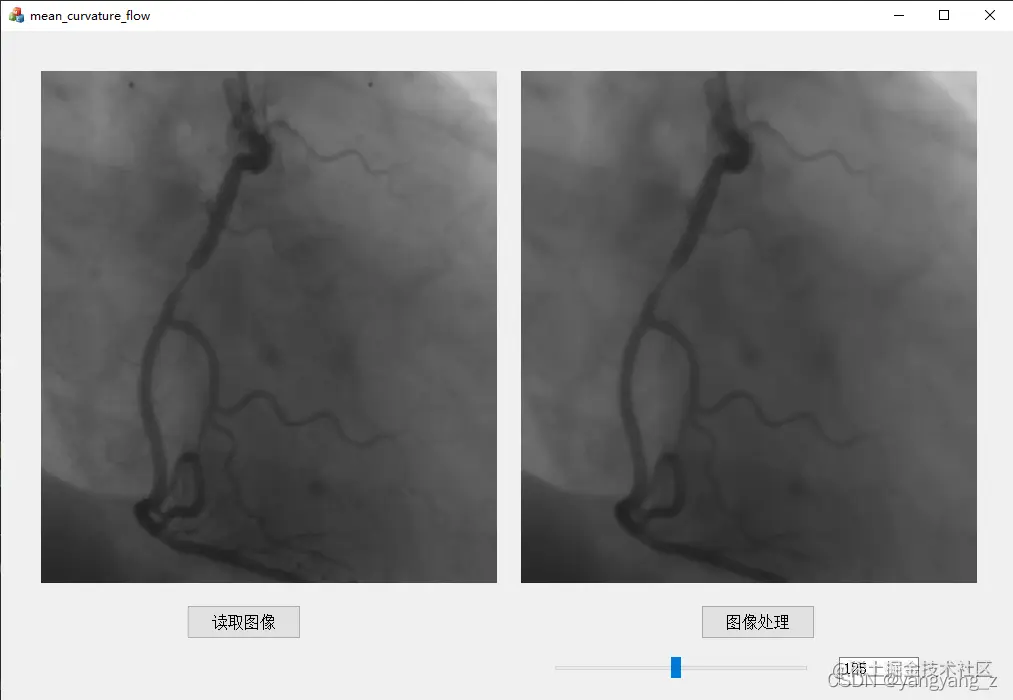

MFC联合Halcon处理效果

使用平均曲率流增强血管造影图像

在这里插入图片描述 注:具体工程代码见MFC联合Halcon处理mean_curvature_flow